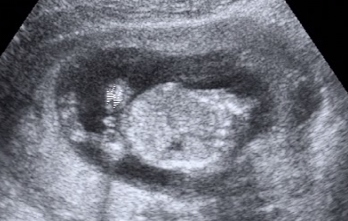

youlcsinak kisfia lesz :) hát nem látszik a képen??? :o szerintem igen... a dokinak is mondtam, hogy ez tuti kisfiú :D igaz, szerint eilyenkor még nem látszik... de szerintem csak rá kell nézni :)